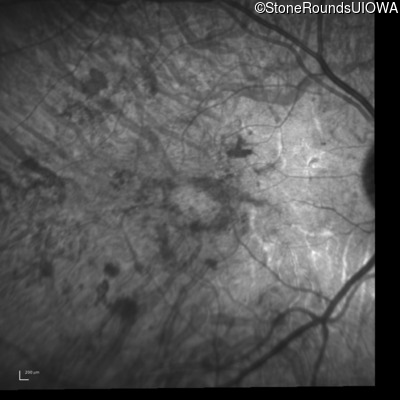

Infrared Fundus Photograph - Right - 20/600 sc

Exemplar